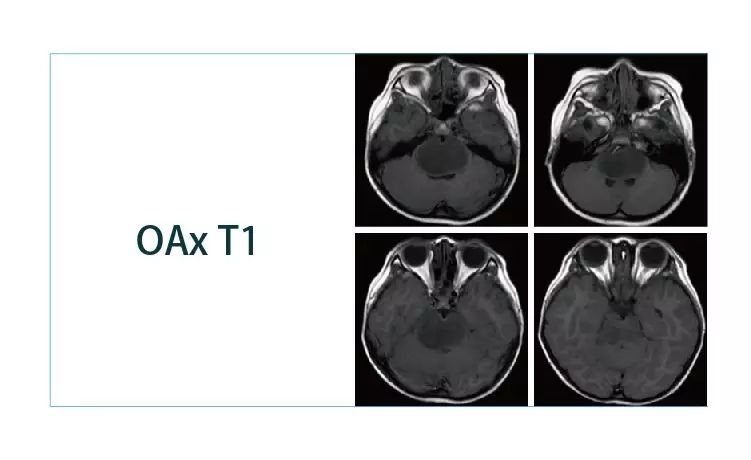

【朗润影像档案】磁共振影像病例分享(编号20190329)